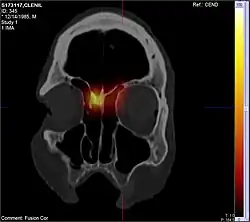

CT scan

CT scan can show the full extent of the polyp, which may not be fully appreciated with physical examination alone. Imaging is also required for planning surgical treatment.[7] On a CT scan, a nasal polyp generally has an attenuation of 10–18 Hounsfield units, which is similar to that of mucus. Nasal polyps may have calcification.[14]

CT scan images after application of radioactive laced nasal steroids using long nozzle. Note the reach of the medication into the area where nasal polyps originate

Endoscopic sinus surgery, advocated and popularized by Professor Stammberger, is often very effective for most people, providing rapid symptom relief. Endoscopic sinus surgery is minimally-invasive and is done entirely through the nostril with the help of a camera. Surgery should be considered for those with complete nasal obstruction, uncontrolled runny nose, nasal deformity caused by polyps or continued symptoms despite medical management.[7] Surgery serves to remove the polyps as well as the surrounding inflamed mucosa, open obstructed nasal passages, and clear the sinuses. This not only removes the obstruction caused by the polyps themselves, but allows medications such as saline irrigations and topical steroids to become more effective.[19] It has been suggested that one of the main objectives in sinus surgery for polyps is to allow delivery of the steroids into those areas of the sinuses where polyps develop, namely, the ethmoid sinuses. Specially designed long nozzles had been developed to use postoperatively to deliver steroids into those areas after sinus surgery for polyps.[20]